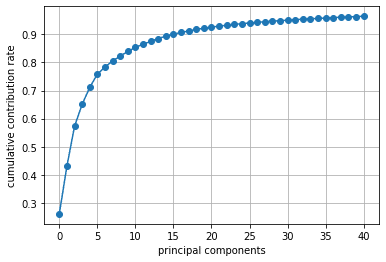

累積寄与率を見ると、第8主成分までで8割を超えていました。

print(np.cumsum(pca.explained_variance_ratio_)) # 累積寄与率

%matplotlib inline

import matplotlib.pyplot as plt

plt.figure()

plt.plot(np.cumsum(pca.explained_variance_ratio_)[:40+1], '-o')

plt.xlabel('principal components')

plt.ylabel('cumulative contribution rate')

plt.grid()

plt.show()